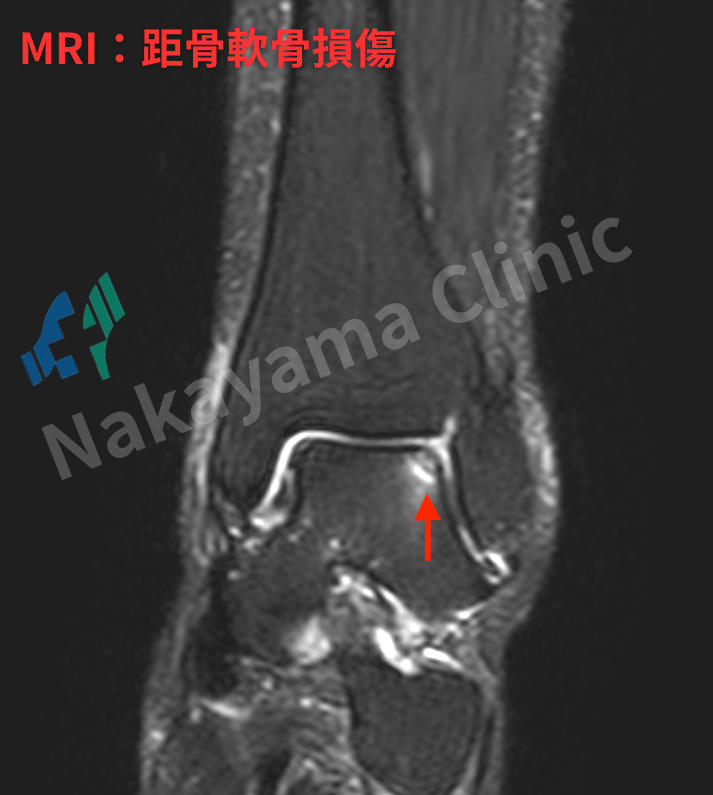

2️⃣ 距骨(きょこつ)の軟骨損傷

これらは、放置されると深刻な後遺症😖(慢性的な痛み、関節の変形など)の原因となります。

特に「踵骨前方突起骨折」は、足を捻った後にいつまで経っても痛みが続く場合の原因として多く見られますが、

レントゲンだけでは非常に見逃されやすい、厄介な骨折なのです。

もちろん、骨折や軟骨損傷が強く疑われる場合には、MRI検査も非常に有用です。